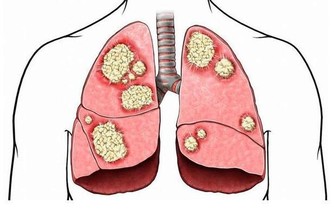

其實,骨質疏鬆和平時所用藥物也有關係,藥物長期使用之下可能造成骨質漸漸流失。

以下藥品有可能造成骨質流失,

因此若平時有長期使用以下藥品且確診為骨質疏鬆症患者,

建議與醫師聯繫,視情況調整用藥,才能做個有「骨氣」的人。

常見可能造成骨質疏鬆的藥物

1、增加維生素D的代謝:Phenytoin(癲癇治療)、Phenobarbital(癲癇治療)。

2、增加骨代謝:Valproicacid(精神科用藥)、Cyclosporin(控制器官移植後排斥作用)、Heparin(血栓性栓塞症及其預防)。

3、減少骨生成:Ifosfamide(抗癌藥)、Prednisolone(緩解發炎及過敏癥狀)。

4、減少血清鈣的濃度:Carbamazepine(癲癇治療、三叉神經痛)。